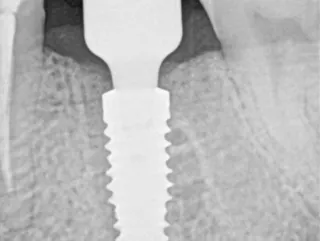

• Radiograph of final crown on Variobase® abutment screw-retained in final position.